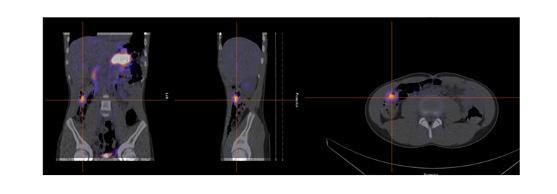

Dans notre expérience, l’étude SPECT-TDM faible permet de confirmer les trouvailles planaires et de mieux le localiser par rapport aux structures normales pour la planification opératoire (figure 7 ). Dans notre expérience également, quoiqu’aucun diverticule de Meckel n’ait été identifié uniquement sur l’étude

Figure 3 : Patient de 2 ans avec rectorragies intermittente depuis 7 mois et anémie. Examen effectué avec préparation pharmacologique de type ranitidine per os. Étude dynamique ( A ) et statique ( B ) en incidence antérieure démontrant un foyer pouvant potentiellement être d’origine rénale au niveau de l’hypochondre droit (flèche). Position antérieure du foyer de captation démontré par l’incidence latérale droite (C) et confirmé par la triangulation en SPECT ( D) et le rendu 3D (E). Mise en évidence d’un diverticule de 2cm contenant de la muqueuse gastrique ulcérée et de la muqueuse pancréatique.

Figure 6 : Patient de 13 ans avec douleurs abdominales mais sans rectorragies. Mise en évidence sur la TDM diagnostic d’une image anormale à la fosse iliaque gauche. Scintigraphie effectuée avec préparation préalable avec famotidine po pendant 2 jours. Sur l’étude dynamique ( A ) apparition d’un foyer au niveau de la fosse iliaque gauche (flèche) de façon concomitante à l’estomac, soit vers la deuxième minute, avant les reins et la vessie qui sont démontrés respectivement à 5 et 9 minutes. Foyer (flèche) en augmentation sur le cliché planaire post miction ( B), confirmé avec la triangulation de l’étude SPECT-TDM où le diverticule est visualisé (C) et le rendu 3D (D).